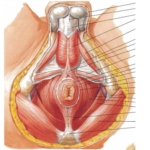

Sin embargo, el suelo pélvico no se compone únicamente de la musculatura.

La mayor parte del suelo pélvico incluye también tejido conjuntivo, entre ellos ligamentos, tendones y fascias, que proporcionan estabilidad, elasticidad y soporte.

La interacción entre estos tejidos y los músculos permite que el suelo pélvico realice funciones esenciales como el control de esfínteres, el sostén de órganos, la estabilidad del tronco y la participación en la vida sexual.

Fuente: Netter. Atlas de anatomía humana